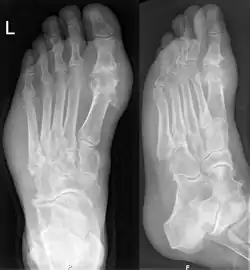

Gicht im Röntgenbild des Fußes. Typische (Haupt-)Lokalisation am Großzehengrundgelenk. Auffallend auch die Weichteilschwellung in der Umgebung des Gelenkes

Nach Ablauf mehrerer Anfälle entwickelt sich eine chronische Gicht mit Zerstörung der Gelenke. Charakteristisch sind im Röntgenbild gelenknahe Stanzdefekte in der Spongiosa (innere Anteile des Knochens), der Gelenkkopf weist deutliche Defekte auf. Die Folgen sind Einschränkung der Leistungsfähigkeit, Harnsäurekristallablagerungen in Gelenken, Gelenkdeformation, Nierensteine, Nierenversagen. Wenn die Gicht in die chronische Phase übergeht, werden die akuten Anfälle oft weniger deutlich und weniger schmerzhaft.